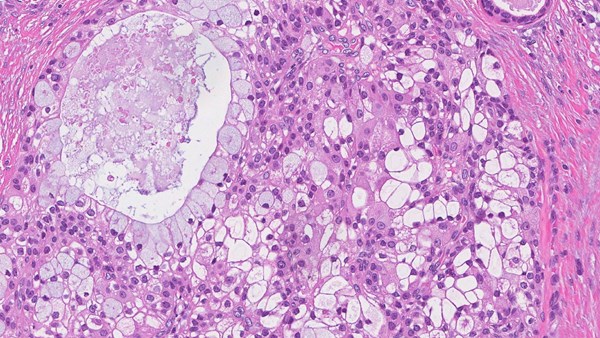

Salivary Gland Cancers

These are a rare group of cancers. They represent less than 5% of all head and neck malignancies and can also present in other areas of the body, including the windpipe, breast, skin and the vulva. Surgery, where possible, followed by radiotherapy is the most common treatment. Supporting research and clinical trials is vital to improve survival and reduce side effects in all patients.